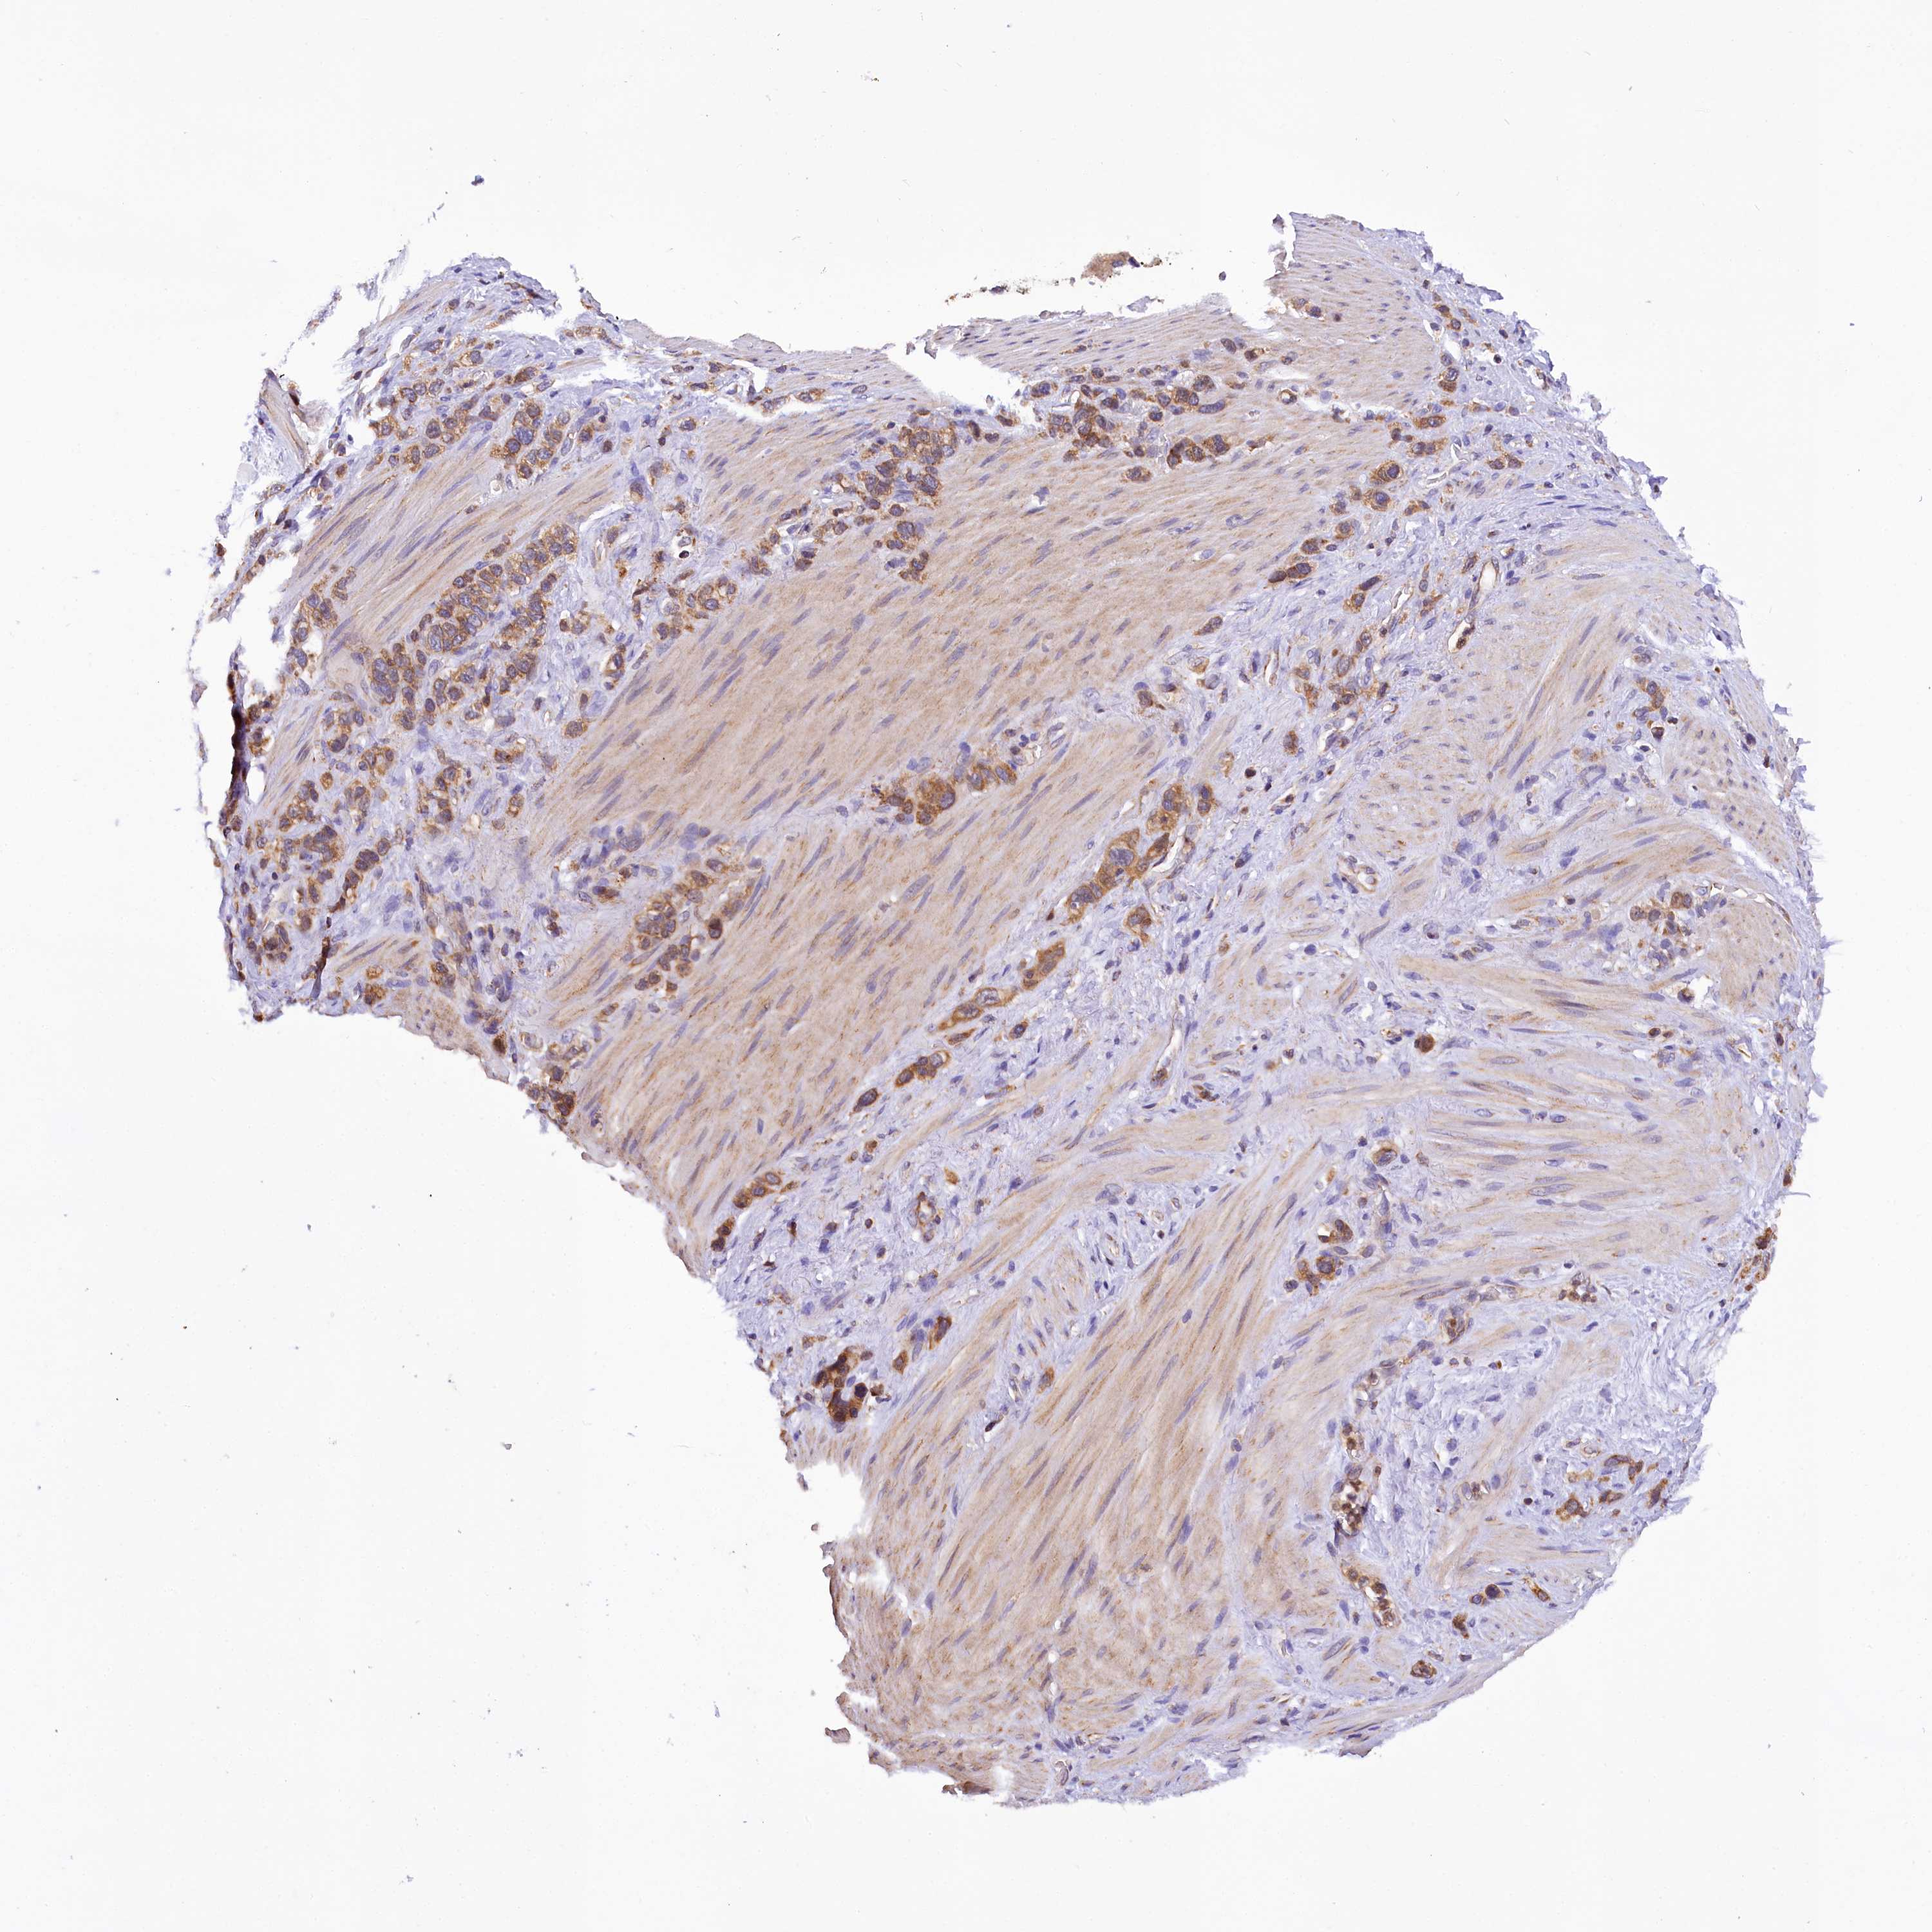

STOMACH CANCER - Protein expressioni

A mouse-over function shows sample information and annotation data. Click on an image to view it in a full screen mode. Samples can be filtered based on level of antibody staining by selecting one or several of the following categories: high, medium, low and not detected. The assay and annotation is described here.

Note that samples used for immunohistochemistry by the Human Protein Atlas do not correspond to samples in the TCGA dataset.

Antibody stainingi

Antibody staining in the annotated cell types in the current human tissue is reported as not detected, low, medium, or high, based on conventional immunohistochemistry profiling in selected tissues. This score is based on the combination of the staining intensity and fraction of stained cells.

Each image is clickable and will lead to virtual microscopy that enables deeper exploration of all samples and also displays staining intensity scores, fraction scores and subcellular localization as well as patient and tissue information for each sample.

Antibody HPA038042

Antibody HPA038043

Staining

High

Medium

Low

Not detected

Intensity

Strong

Moderate

Weak

Negative

Quantity

>75%

75%-25%

<25%

None

Location

Nuclear

Cytoplasmic/membranous

Cytoplasmic/membranous,nuclear

Adenocarcinoma, NOS

Adenocarcinoma, High grade